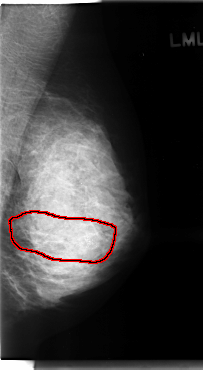

C_0120_1.LEFT_MLO

FILE: C_0120_1.LEFT_CC.OVERLAY

TOTAL_ABNORMALITIES 1

ABNORMALITY 1

LESION_TYPE CALCIFICATION TYPE AMORPHOUS-PLEOMORPHIC DISTRIBUTION SEGMENTAL

ASSESSMENT 5

SUBTLETY 5

PATHOLOGY MALIGNANT

TOTAL_OUTLINES 1

BOUNDARY